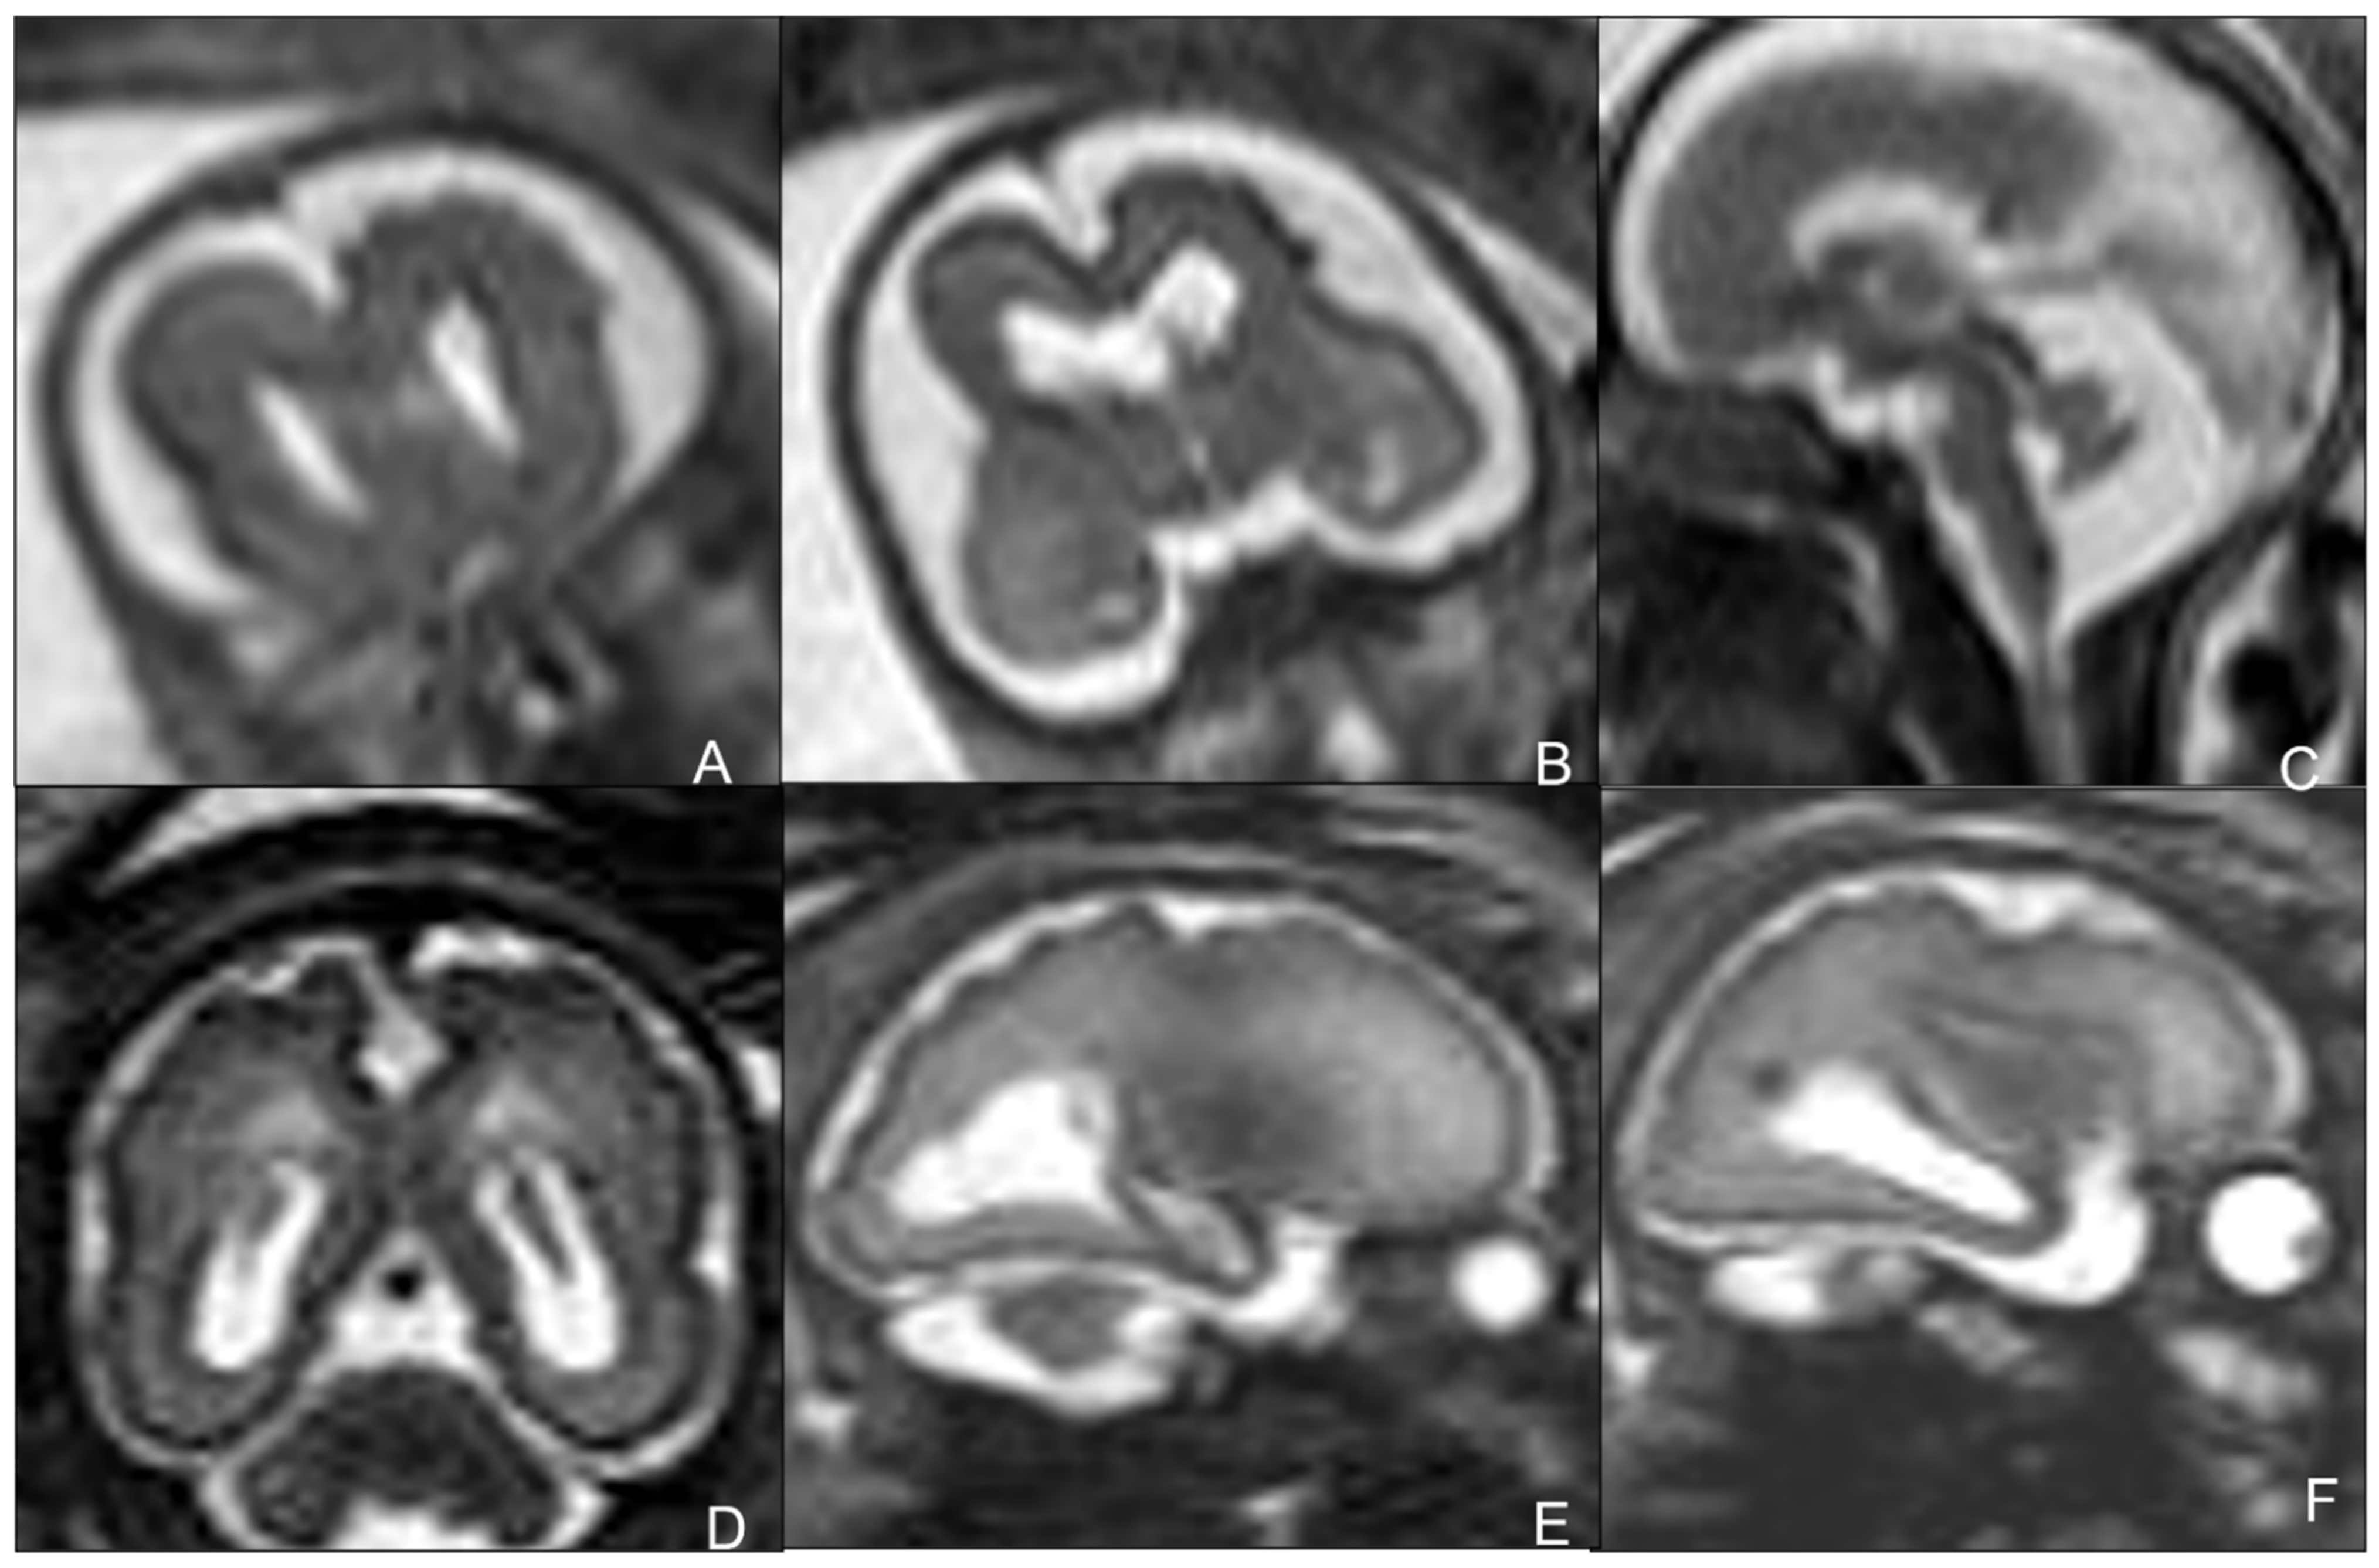

2.2. Toxoplasmosis

- Diebler, C.; Dusser, A.; Dulac, O. Congenital toxoplasmosis. Clinical and neuroradiological evaluation of the cerebral lesions. Neuroradiology 1985, 27, 125–130. [Google Scholar] [CrossRef]

- Jacquemard F Ultrasonographic signs of congenital toxoplasmosis. Arch. Pediatr. 2003, 10 (Suppl. S1), 35–38.

- Lago, E.; Baldisserotto, M.; Filho, J.H.; Santiago, D.; Jungblut, R. Agreement between ultrasonography and computed tomography in detecting intracranial calcifications in congenital toxoplasmosis. Clin. Radiol. 2007, 62, 1004–1011. [Google Scholar] [CrossRef] [PubMed]

- Triulzi, F.; Baldoli, C.; Parazzini, C.; Righini, A. Perinatal Neuroradiology; Springer: Berlin/Heidelberg, Germany, 2016. [Google Scholar]